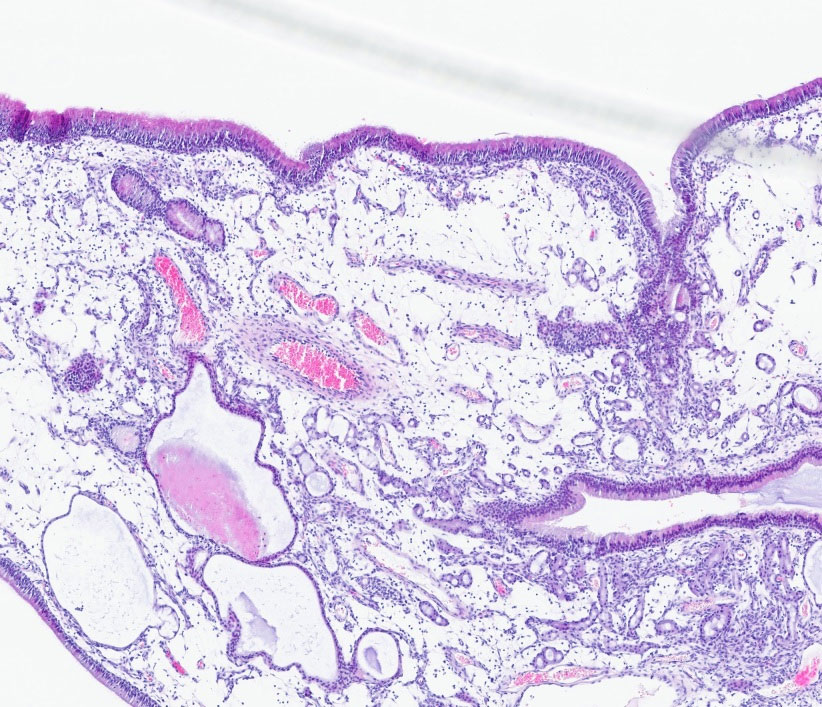

Abb. 1: Histologie eines nasalen Polypen eines Hundes, 4er Vergrößerung, HE-Färbung

Bildquelle: Laboklin

Zudem sind bei der Katze nasopharyngeale Polypen mit Entstehung im Pharynxbereich, in der Tuba auditiva oder der Bulla tympanica als eigenständige Entität beschrieben. Die genaue Pathogenese ist bei beiden unklar. Nasale und nasopharyngeale Polypen sind exophytische Proliferationen stark ödematisierten und teils myxoiden, fibrovaskulären Stromas, bedeckt von gut differenziertem respiratorischem Epithel (Abb. 1). Einzelne Drüsen und Lymphgefäße im Stroma sind häufig dilatiert. Sie sind mit turbinaler Destruktion assoziiert und Rezidive sind möglich.